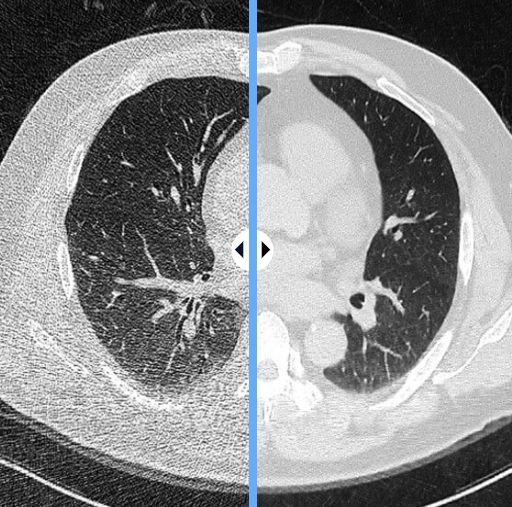

[서울-뉴시스] 8일 클라리파이에 따르면 서울대어린이병원 연구팀은 클라리파이가 개발한 의료AI 솔루션 'ClariCT.AI'를 활용한 결과 초저선량 CT에서도 영상 품질이 일반 선량 CT와 유사하고 진단 성능 또한 유지할 수 있다고 보고했다. 사진은 클라이파이의 의료AI 솔루션 사용 전(왼쪽)과 후 모습. (사진=클라리파이 제공) 2025.03.07. [email protected] *재판매 및 DB 금지

연구팀은 클라리파이가 개발한 의료AI 솔루션 'ClariCT.AI'를 활용한 결과 초저선량 CT에서도 영상 품질이 일반 선량 CT와 유사하고 진단 성능 또한 유지할 수 있다고 보고했다. 이번 연구로 AI 기술을 활용하면소아환자들의 두부 CT 촬영에서 의료 방사선량을 줄일 수 있음이 입증됐다.

연구결과 초저선량 CT에 AI 재구성을 적용한 그룹에서는 영상품질이 향상됐고 두개골 조기융합증 진단 성능에도 일반 선량 CT 촬영 그룹에 비해 차이가 없었다. 반면, 초저선량 CT에 AI 재구성을 적용하지 않았을 경우에는 영상품질이 저하됐다.